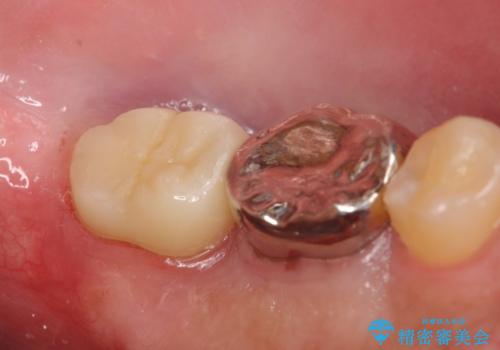

- 左下7の歯しみる、被せ物を被せてもすぐに外れてしまうといらっしゃった方の症例です。

左下に被せ物を被せるクリアランス(補綴のための上下のスペース)ないため、十分な歯冠長を確保するため歯冠長延長術を行いました。

その後歯肉の回復を待ち、フルジルコニアクラウンにて補綴を行いました。